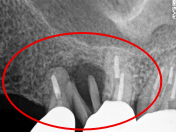

右下奥の歯が、グラグラして噛むと痛い。

治療内容

歯根の周りの骨が全く無い状態でしたので、保存することができず抜歯しました。3本歯がないところに2本インプラントを埋入しました。

Before

※赤丸を抜歯しました。

After